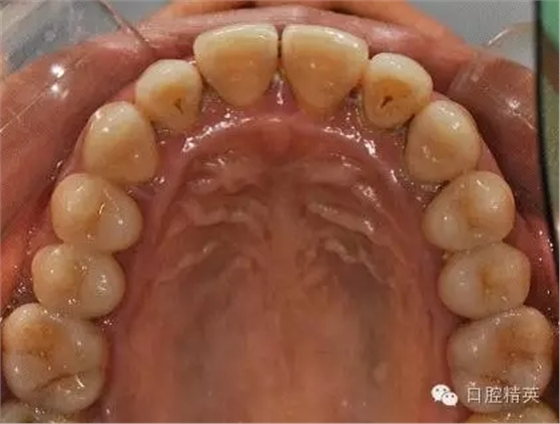

X-ray:

齦下刮治術(shù)(subgingival scaling),即根面平整術(shù)(root planing),是用比較精細的齦下刮治器刮除位于牙周袋內(nèi)根面上的牙石和菌斑。做齦下刮治時,醫(yī)生會使用一些專用去除袋內(nèi)結(jié)石的器械,刮除袋內(nèi)結(jié)石、細菌和受細菌感染組織。由于進行該項操作需將器械伸入袋的深部組織內(nèi),既要刮盡齦下牙石(有時還要刮除牙根表面的壞死組織),又要盡量避免多損傷牙周組織。這就需要有較高的技巧,只有經(jīng)過專門訓(xùn)練的專業(yè)技術(shù)人員才能完成。

治療后:炎癥得到控制,牙周袋已消除,松動度有所改善。